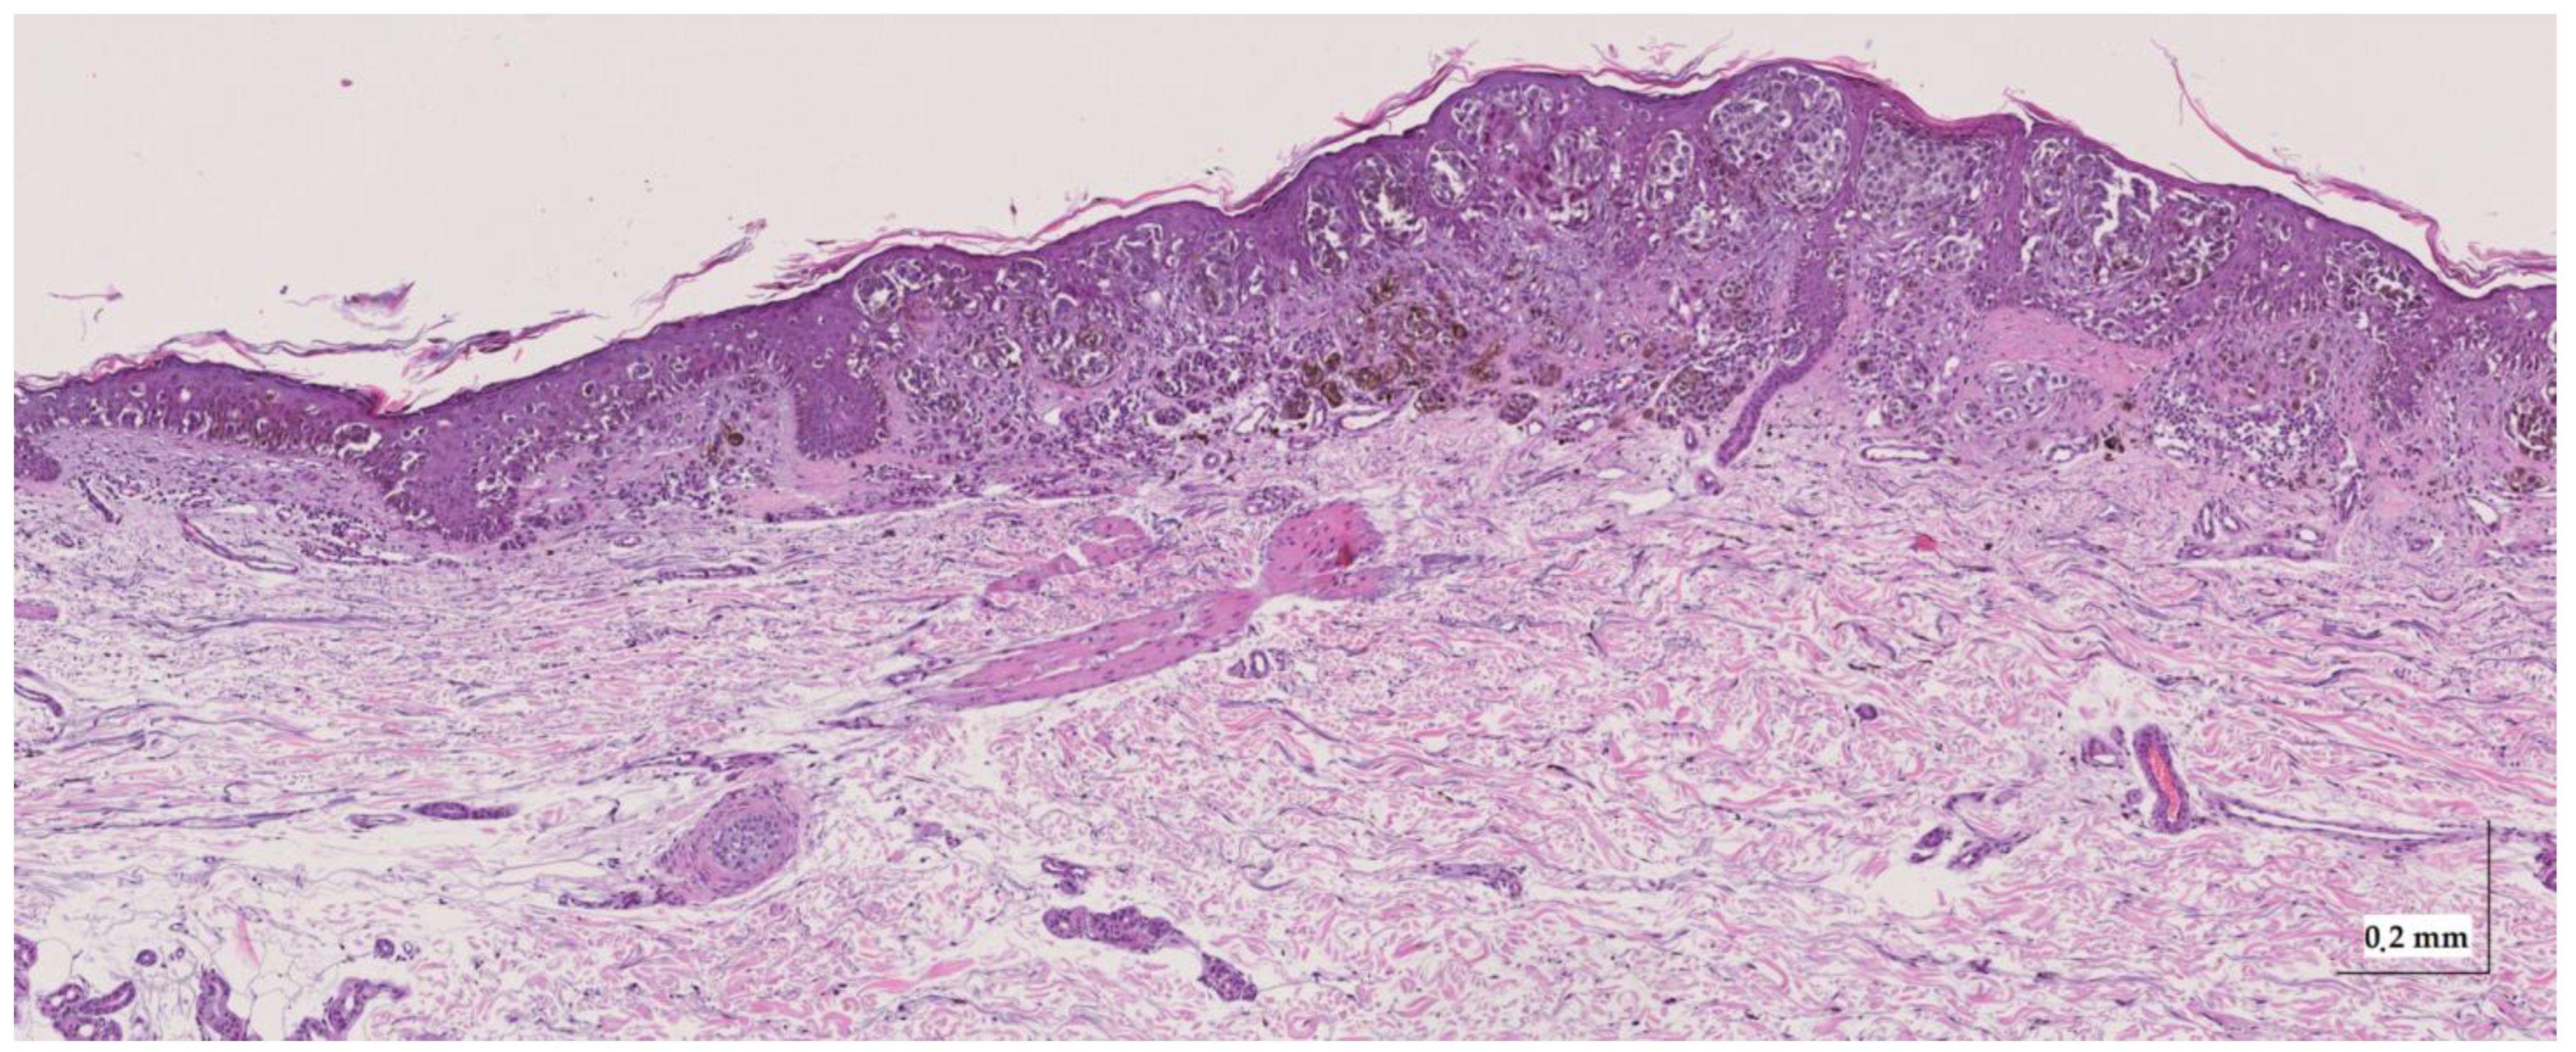

Appendix A. Selected Cases Studies’ HE Histopathological Images (Limited to OCT FOV)

| Intradermal nevus (IN) Case 2 | Localization: left dorsal |

![]() | ![]() |